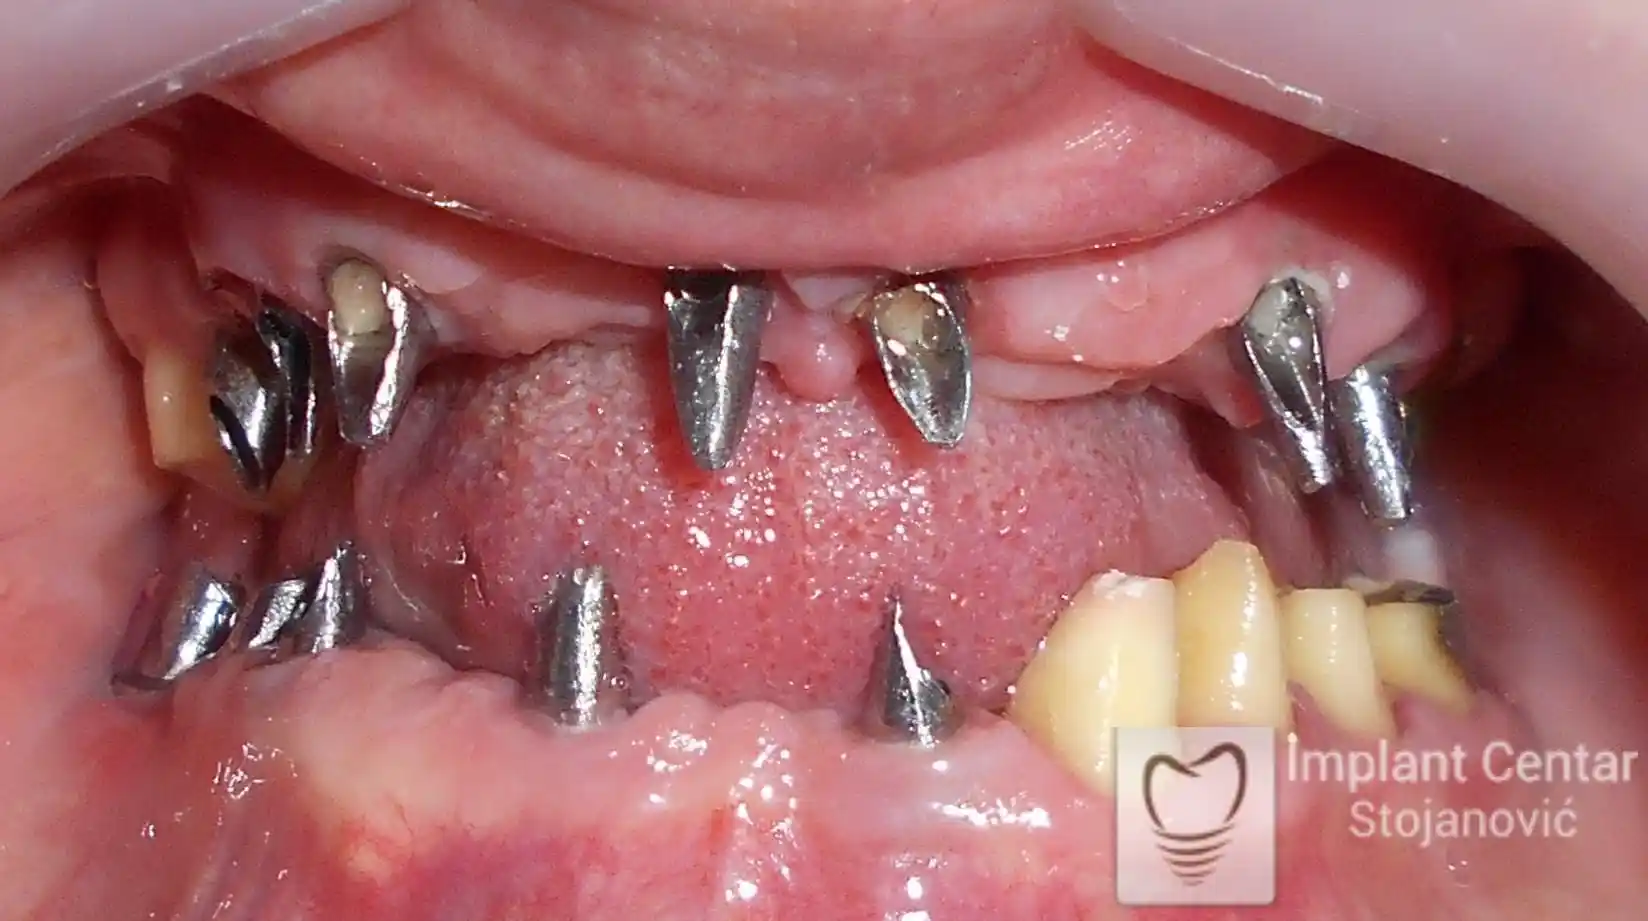

Pacijent sa rascepom usne, nepca i alveolarnog grebena uspešno je rehabilitovan fiksnim protetskim radom na implantatima. Pre dolaska u našu ordinaciju, pacijent je u gornjoj vilici nosio totalnu protezu preko preostalih zuba, dok je u donjoj vilici bio zbrinut parcijalnom mobilnom protezom. Tokom višegodišnje potrage za adekvatnim rešenjem, pacijent nije uspeo da pronađe zadovoljavajuću terapijsku opciju ni u zemlji ni u inostranstvu.

Nakon detaljnog kliničkog pregleda i analize radioloških snimaka, izrađen je sveobuhvatan plan terapije sa ciljem uklanjanja mobilnih proteza i postizanja maksimalne funkcionalne i estetske rehabilitacije. Zbog loše biološke vrednosti preostalih zuba, doneta je odluka o njihovom vađenju i ugradnji dentalnih implantata.

Poseban terapijski izazov predstavljalo je premošćavanje defekta nastalog usled rascepa, kao i ograničena količina raspoložive kosti u gornjoj vilici. Primenom većeg broja implantata i odgovarajućih procedura nadoknade kosti, postignuta je stabilna osnova za fiksni protetski rad.

Tokom perioda oseointegracije, pacijent je bio zbrinut fiksnim privremenim krunicama, čime je već pet dana nakon intervencije obezbeđena potpuna funkcionalna i estetska rehabilitacija. Nakon završetka perioda integracije implantata, izrađeni su definitivni cirkonijum-keramički mostovi na implantatima.

Pacijent je izuzetno zadovoljan postignutim rezultatom, navodeći da po prvi put jasno oseća svoje nepce tokom žvakanja, kao i da se smeje sa punim samopouzdanjem.